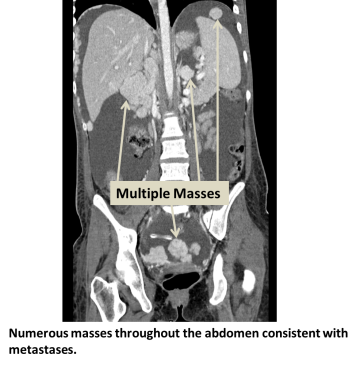

Diagnosis

When primary cancer is present, a physician may also check for metastatic liver cancer using:

- CT scan